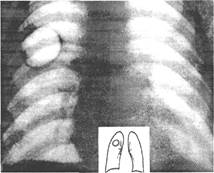

Основным методом диагностики есть рентгенологический (Рис. 11)

Рис. 11 Врожденная киста верхней доли правого легкого: определяются четкие контуры воздушного образования